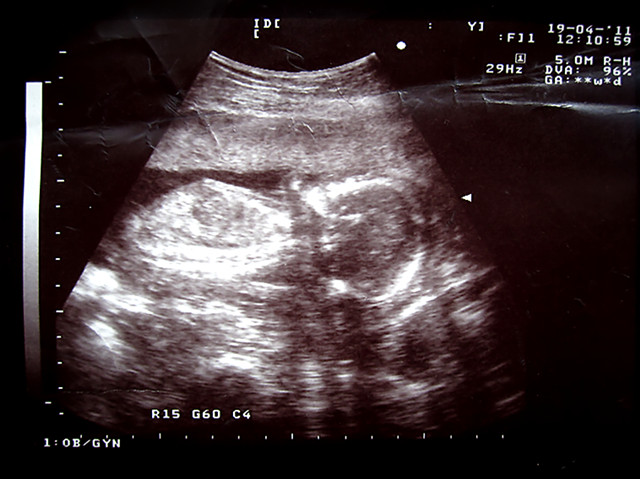

4.19 第四次B超

这次太赶时间了 拿了照片就走

结果到家才发现照片上没有任何信息

有经验的麻麻能不能从B超图上看出我家Sheyla多高啊

医生说了 90%是女生